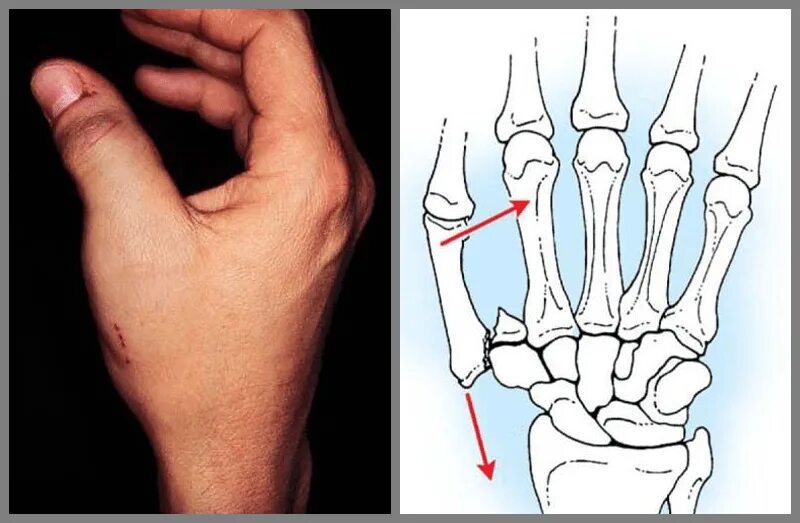

Как определить перелом руки